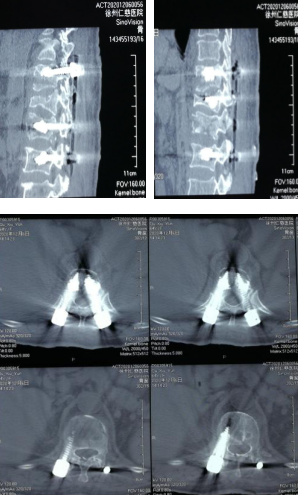

术后CT影像